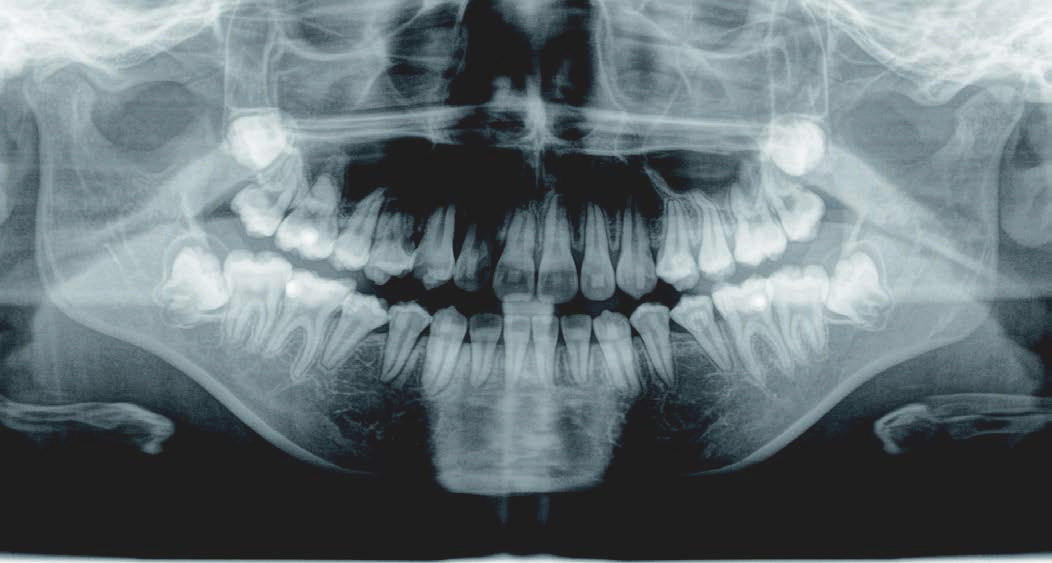

これから生えてくる永久歯のスペースがなく、歯が並ぶ余地がほとんどありませんでした。

さらに、上からあごの骨を見たところ、中央がくびれた“ひょうたん型”に変形しており、あごの成長にも偏りが見られました。

診断の結果、前歯の中心も少し左にずれており、特に犬歯が生えるスペースが足りない状態でした。

飲み込むときに下くちびるに力が入り、顔の左側にゆがみが出ている様子も確認できました。

治療を終えて

犬歯が歯ぐきの中に埋まっていたため、透明のマウスピース型装置で生えるスペースを作り正しい位置に導きました。もちろん抜歯せずに歯並びを整えることができました。お口の中がとても小さく、型どりの際にオエッとなる反応が強く、当時は装置を作るのが大変でした。しかし現在では3Dスキャナーと3Dプリンターを活用しスムーズに治療できます。

主訴・治療内容 「あごが小さいから、歯がきれいに並ばない」と他院で言われ永久歯を抜く矯正をすすめられていました。

本当に非抜歯で治療できるのか心配されていましたが、治療方法を丁寧にご説明し、お任せいただきました。

治療期間 5年

費用 550,000円(税込)